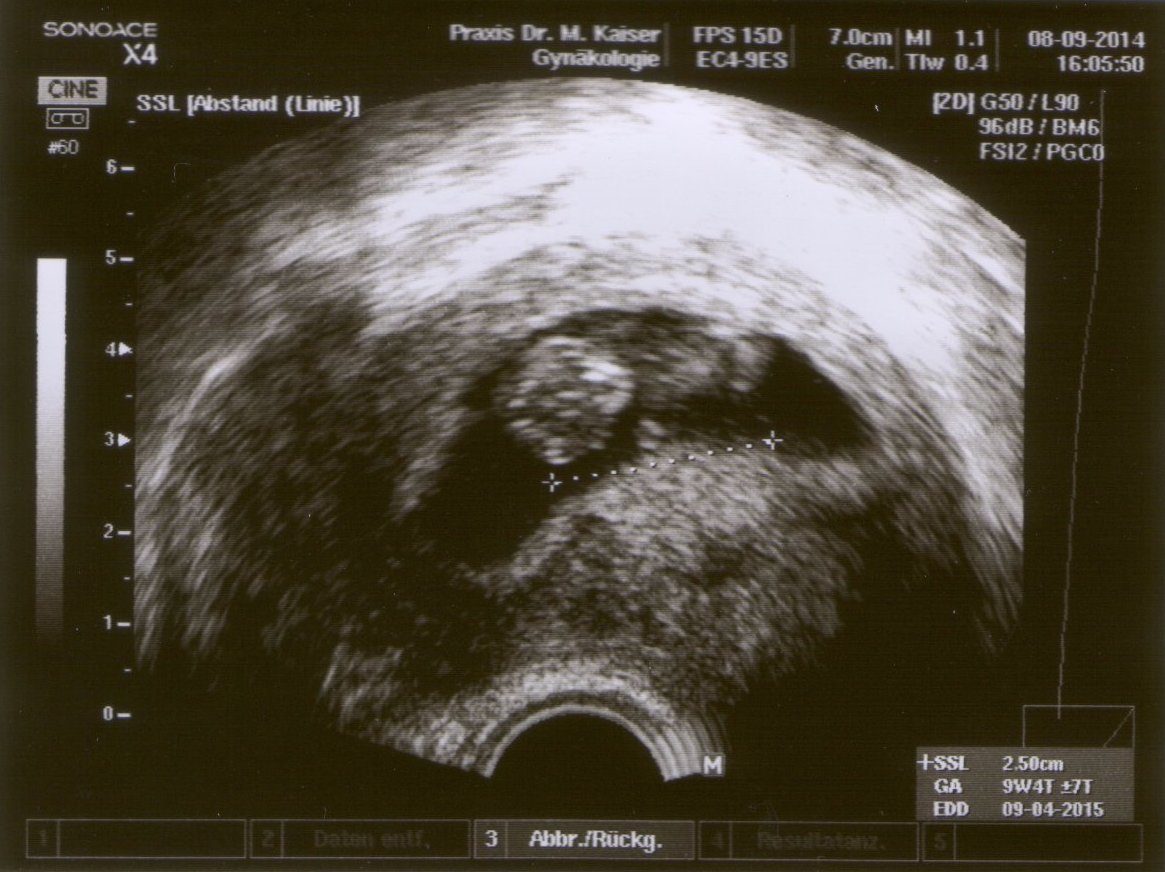

Bei der heutigen Ultra-Schall-Untersuchung wollte sie uns einfach nicht ihr Gesicht zeigen. Dafür hat sie aber schon einmal gewinkt.